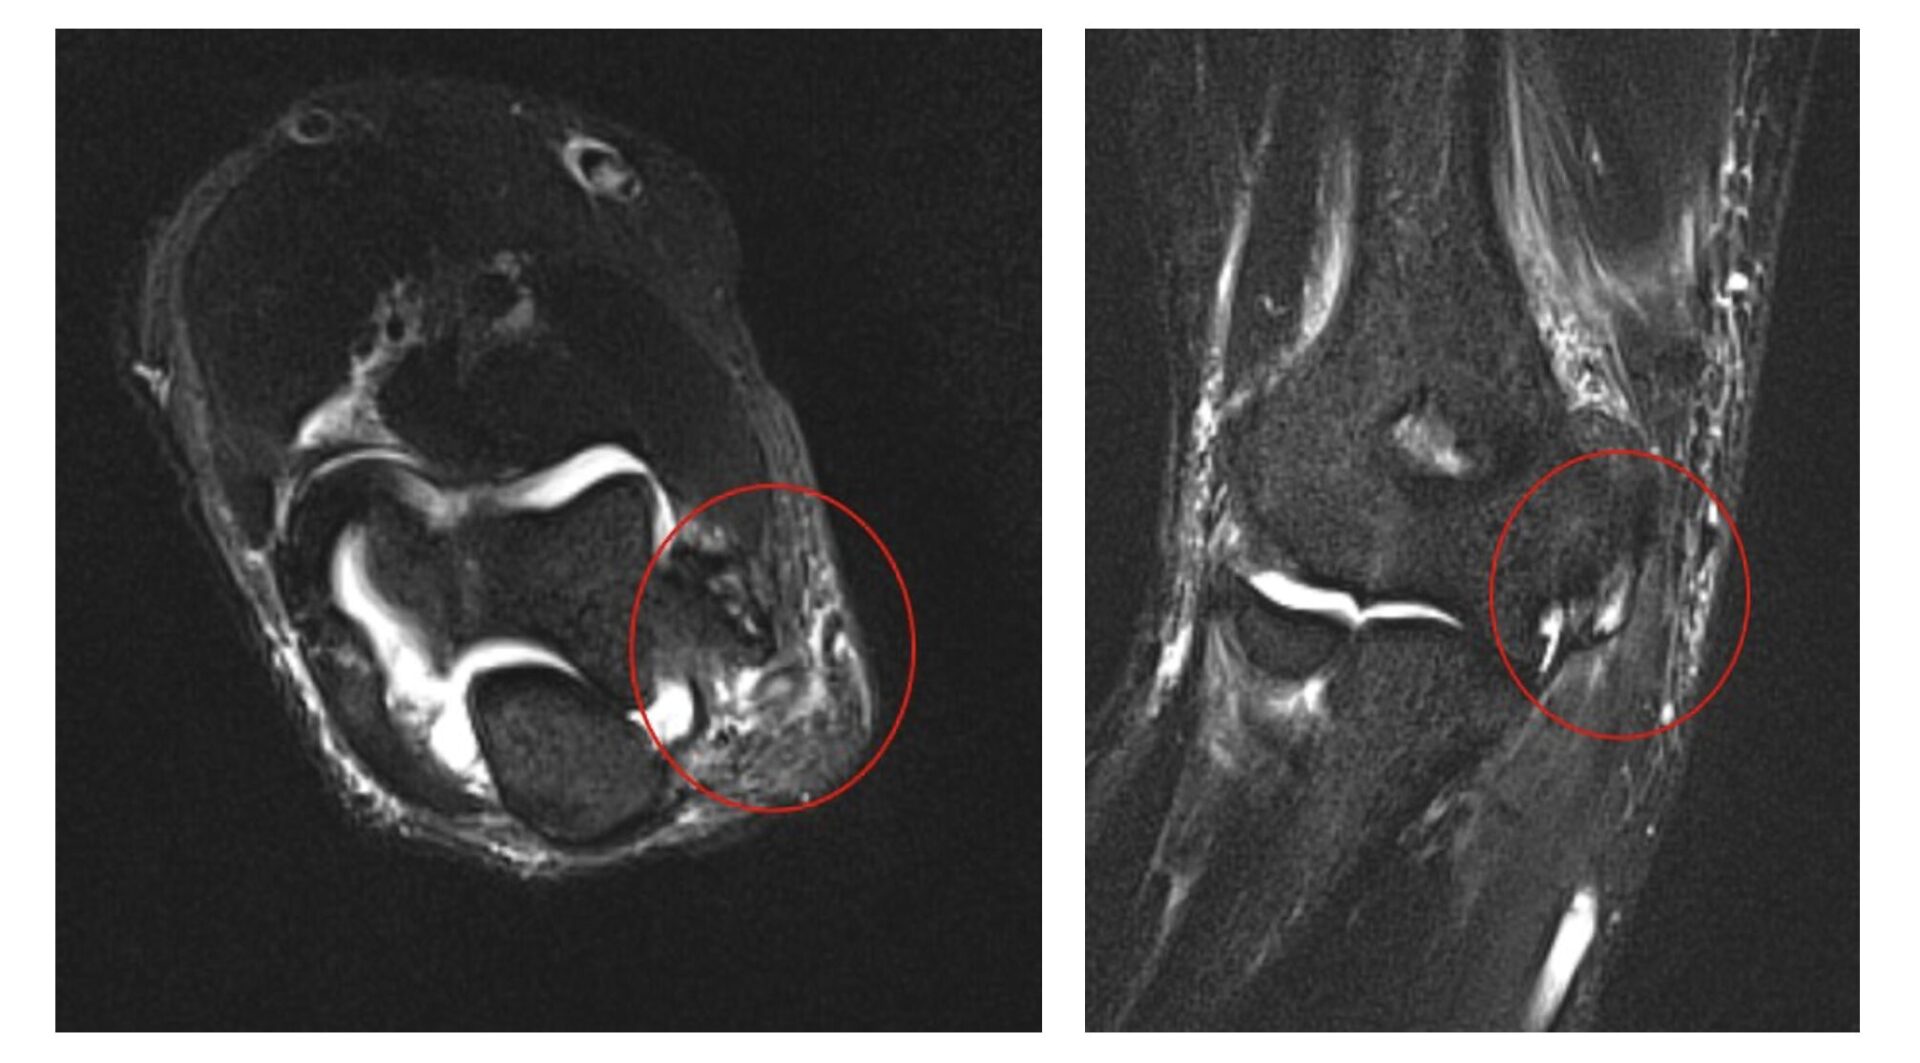

- MRI:腱の付着部に変性や損傷を確認します。その他関節内や骨、靭帯の評価も行います。

実際に撮影したゴルフ肘のMRI画像